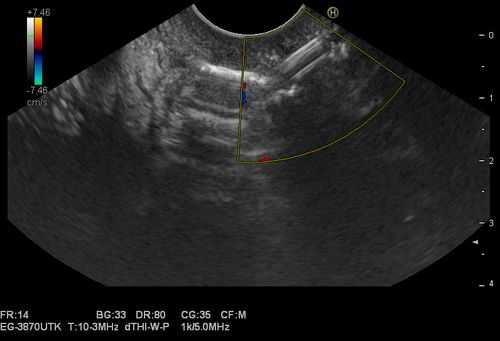

1. Проведение в желудок эхоэндоскопа OlympusGF-UE 160 и эндоскопическое ультразвуковое сканирование органов брюшной полости для определения зоны контакта стенки кисты со стенкой желудка (рис. 1). Рис. 1. Эхоэндоскопия и ультразвуковая визуализация панкреатической псевдокисты в теле поджелудочной железы (случай 1).

При эндосонографии (эндоУЗИ) в области головки поджелудочной железы визуализировано анэхогенное образование с четкими неровными контурами неправильной продольной формы, размерами 3,1х10 cм, прилежащее к воротной вене - постнекротическая киста с преимущественно внеорганным расположением (рис. 3).